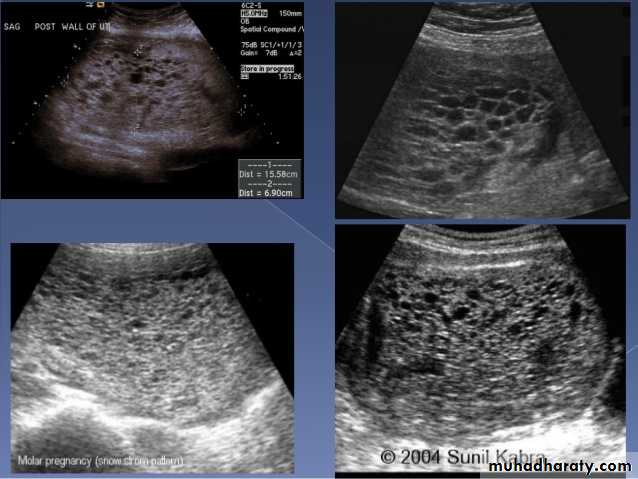

Molar pregnancy

Gestational trophoblastic disease (GTD) results from abnormal proliferation of trophoblastic tissue, and encompasses a wide spectrum of diseases, including:hydatidiform mole

complete mole

partial mole

invasive mole

Chorio carcinoma (gestational choriocarcinoma)

Radiographic features

Ultrasoundenlarged uterus

classic sonographic appearance is that of a solid collection of echoes with numerous small (3-10 mm) anechoic spaces (snowstorm appearance).

the molar tissue demonstrates the punch of grapes sign which represents hydropic swelling of trophoblastic villi.